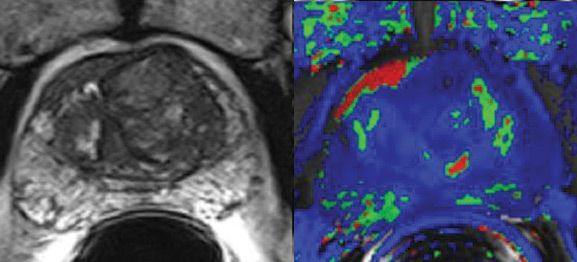

Diffusion-weighted MRI is the most effective MRI technique to detect and evaluate patient response to platinum-based neoadjuvant chemotherapy for late-state ovarian cancer.